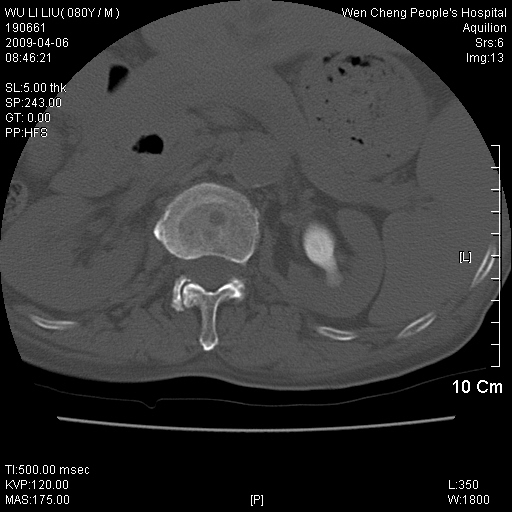

以下是引用zjzjr在2009-4-7 12:13:00的发言:[br]支持多发性转移瘤,右股骨颈骨折,腰椎亦有压缩性骨折.肝内胆管结石伴胆内外胆管扩张,左肾结石.

以下是引用liaoqiang在2009-4-7 8:44:00的发言:[br]考虑多发性骨髓瘤伴肝肺转移、肝内胆管结石、左肾结石、右股骨颈骨折。

以下是引用余辉在2009-4-7 8:52:00的发言:[br]椎骨及骨盆骨质疏松,骨破坏主要累及椎体,各骨破坏较广泛,各病灶边缘均较清晰锐利,血沉增快,白细胞增高.支持考虑多发骨髓瘤,建议查本尿周氏蛋白.[br]胆内胆管及左肾结石[br]右股骨颈骨折,考虑病理性